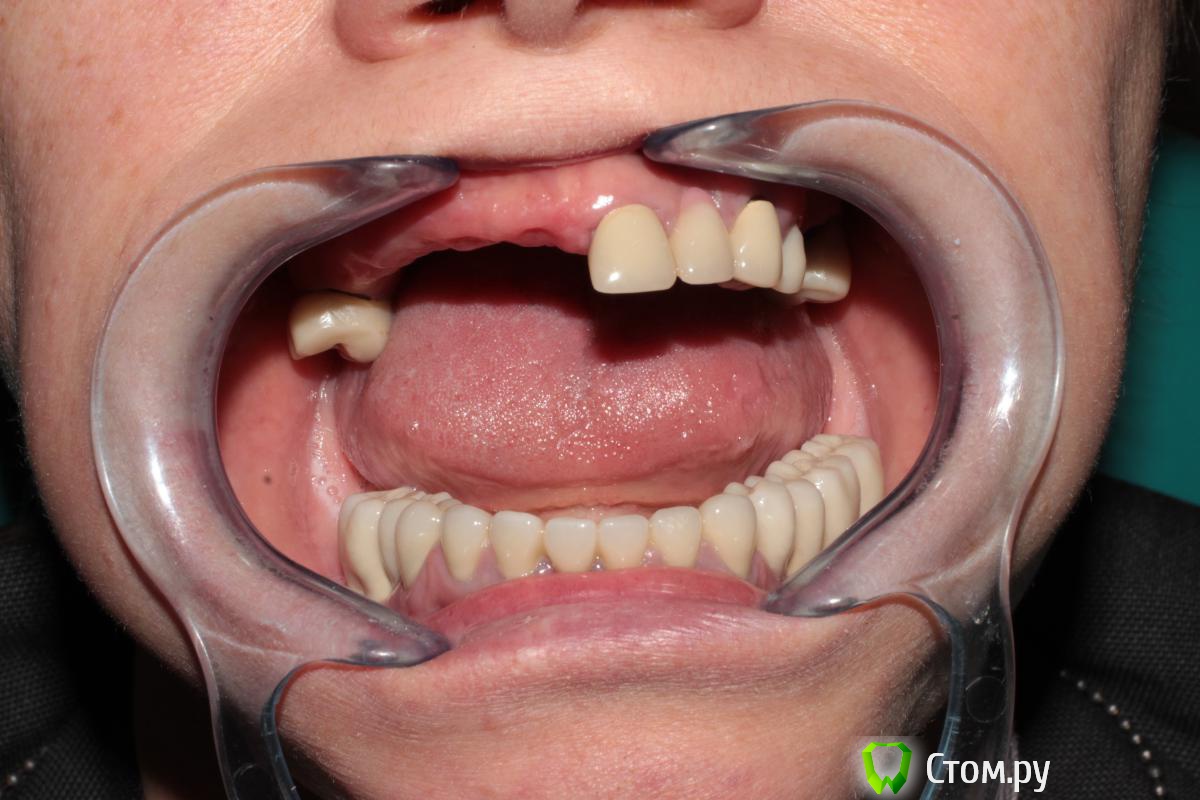

biv29 Опубликовано 30 апреля, 2014 Поделиться Опубликовано 30 апреля, 2014 (изменено) Уважаемые коллеги, прошу вашей помощи в составлении плана комплексной реабилитации пациентки.Пациентка 1962 г.р., 2 года назад были установлены имплантанты на н/ч, осуществлено протезирование (работал другой стоматолог-ортопед). Имеется вертикальная резорбция кости н/ч, рецессия десны, оголение имплантантов.На в/ч сохранены 17, 21, 23, 24, 27. Установлен ЧСПП. 21-23 МК-мостовидный протез (коронка 23 не доходит до десневого края). 24 - временная пластмассовая коронка.Имеется снижение высоты прикуса.- Я склоняюсь к следующему варианту работы:удаление 17, 21, 23, 24, 27; проведение синус-лифтингов с двух сторон, аугментация, установка имплантантов; временное протезирование на время реабилитации после операции, временное протезирование на пластмассовых коронках, постоянное протезирование МК.1. При этом плане возникает вопрос о временном протезировании сразу после хирургического вмешательства. Имплантолог против установки ПСПП на в/ч. Как поступить в этом случае? Использовать ли стабилизацию ПСПП и его фиксацию на мини-имплантантах? Достаточно ли будет мягкой подкладки на внутренней поверхности ПСПП?2. Считаете ли целесообразным осуществить протезирование сначала на в/ч без переделки орт. конструкций на н/ч? 3. 21, 23, 24 - стоит удалять или есть вероятность, что еще послужат? 4. Какой план протезирования вы бы предложили в данной клинической ситуации? Заранее спасибо за возможные ответы. Изменено 30 апреля, 2014 пользователем biv29 Ссылка на комментарий

biv29 Опубликовано 30 апреля, 2014 Автор Поделиться Опубликовано 30 апреля, 2014 1. Фото в прикусе сейчас есть только на моделях (см. вложение). При необходимости приглашу пациентку и сделаю дополнительно.2. Эстетика важна, но альтернативные варианты в пределах разумного можно обговорить. Главное неудобство для пациентки - съемный протез на в/ч. Ссылка на комментарий